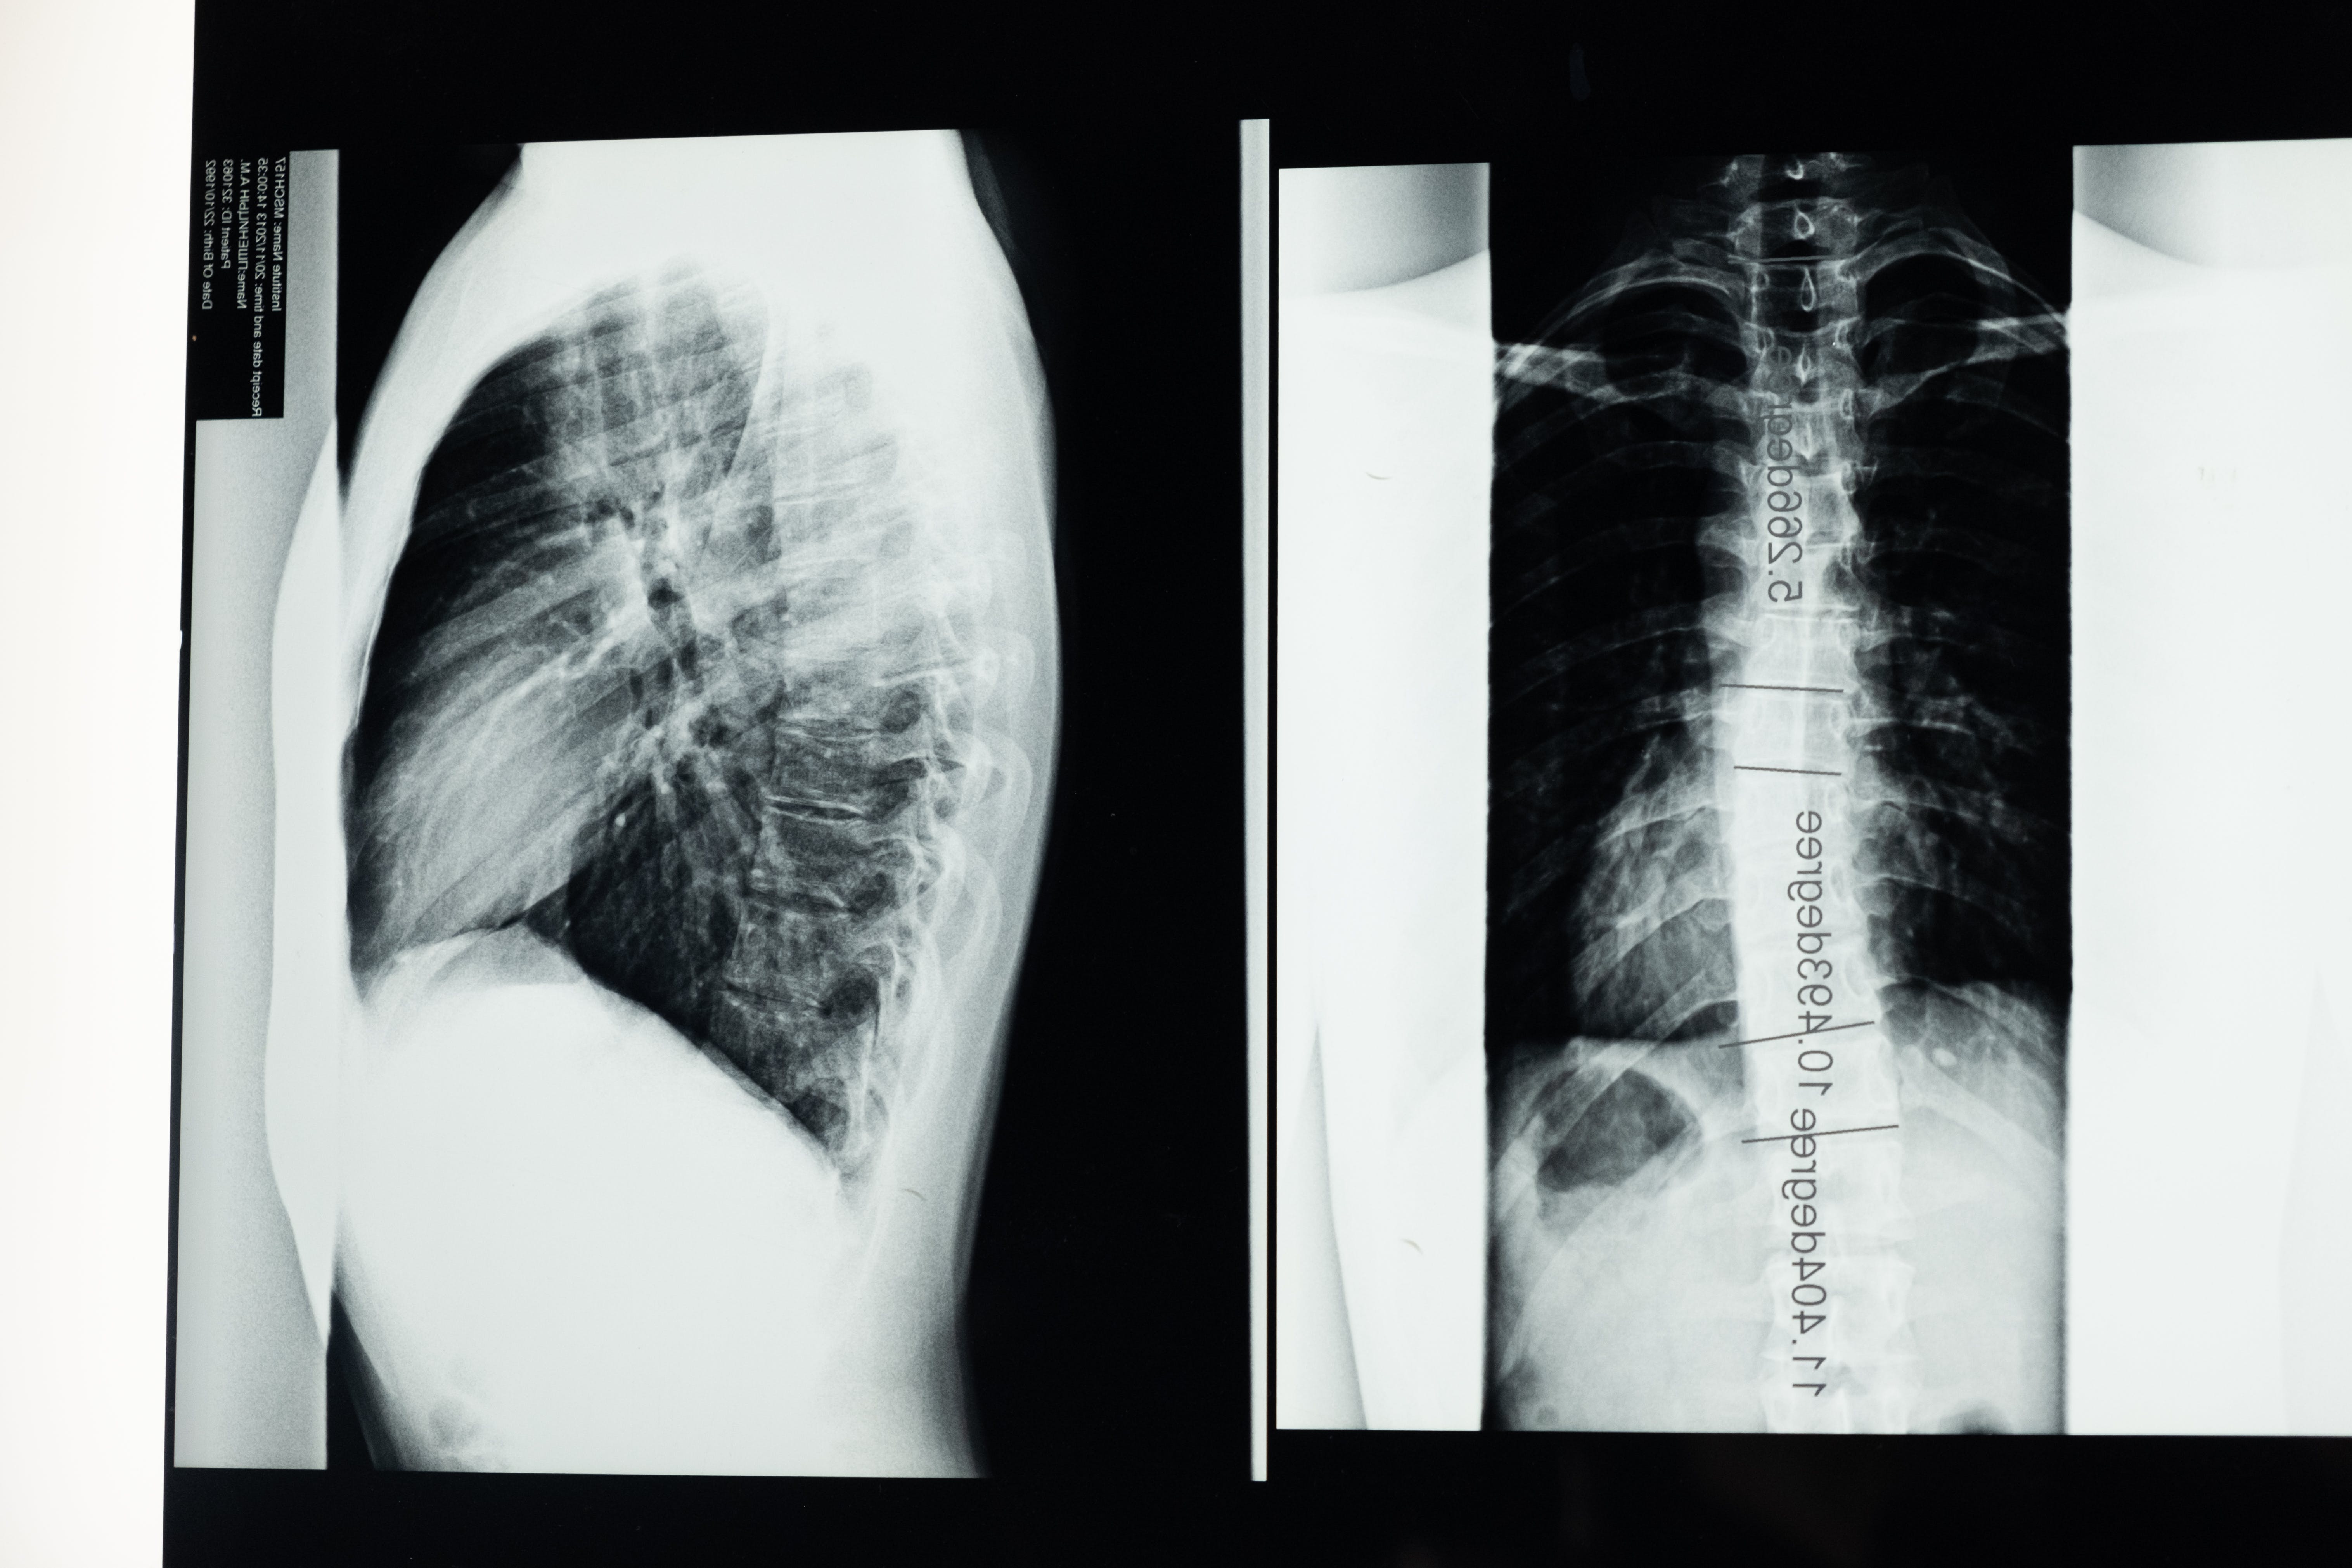

결핵 예방은 강력한 전략에 달려 있습니다. 예방접종, 특히 BCG(Bacillus Calmette-Guérin) 백신은 특히 유병률이 높은 지역에서 보호를 제공합니다. 잠복성 결핵 감염을 확인하고 치료하면 활동성 결핵으로 진행될 위험이 줄어듭니다. 활동성이 있는 경우에는 장기간에 걸쳐 항생제를 병용하는 것이 표준 치료법이 됩니다. 재발과 약물 내성 균주의 출현을 예방하려면 처방된 요법을 준수하는 것이 가장 중요합니다. 공중 보건 계획은 중추적인 역할을 합니다. 교육 캠페인, 개선된 의료 인프라, 사회 경제적 격차 감소는 결핵 통제에 기여합니다. 이 회복력이 강한 적과 맞서 싸우려면 전 세계적인 규모의 협력 노력이 필수적입니다. 결핵의 이야기는 아직 끝나지 않았습니다. 그 지속성은 지속적인 연구, 인식 및 글로벌 협력의 필요성을 강조합니다. 영상 및 실험실 검사를 포함한 의학적 평가를 통한 조기 진단은 질병의 효과적인 관리와 확산 방지에 매우 중요합니다. 결핵의 복잡성을 탐색하면서 우리는 증상을 치료할 뿐만 아니라 결핵의 존재를 영속시키는 사회 경제적 요인도 해결해야 합니다. 결핵에 맞서 단결된 전선을 조성함으로써 우리는 결핵을 역사의 기록으로 남겨 결핵의 영향이 줄어들고 삶이 더 이상 결핵의 그늘 아래 있지 않게 되는 것을 목표로 합니다.